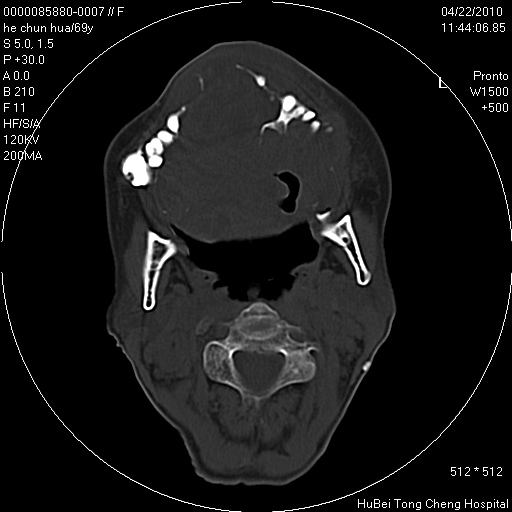

标题: CT25937:女,69Y

硬腭部包块十余年,渐进性增大。